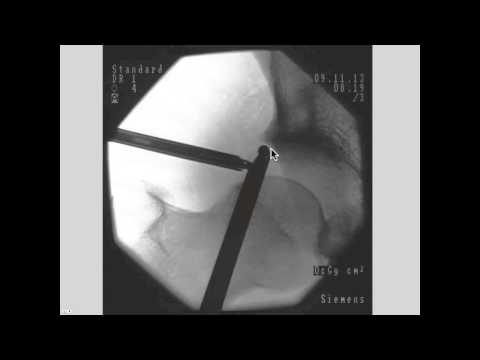

Hip Impingement & Arthroscopic Treatment

Dr. Lane explains hip impingement or FAI in the athlete and how it is treated with minimally invasive techniques. A case example of a 17 year old basketball player is presented with preoperative exam and xrays, surgery video, and postoperative results.